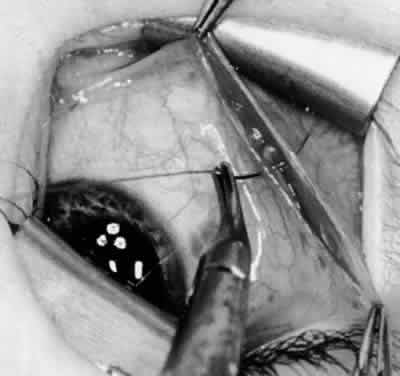

Fig. 24. The eyelid speculum is removed and a Desmarres lid retractor is placed inferiorly. The inferior oblique muscle is drawn superiorly and nasally. The fusiform expansion of the inferior oblique muscle is evident on the posterior border, where the nerve to the inferior oblique muscle and artery and vein enter the inferior oblique muscle. The Stevens muscle hook is used to hook the neurovascular bundle.

Fig. 25. The hook is advanced further for identification of the neurovascular bundle on the inferior oblique muscle.